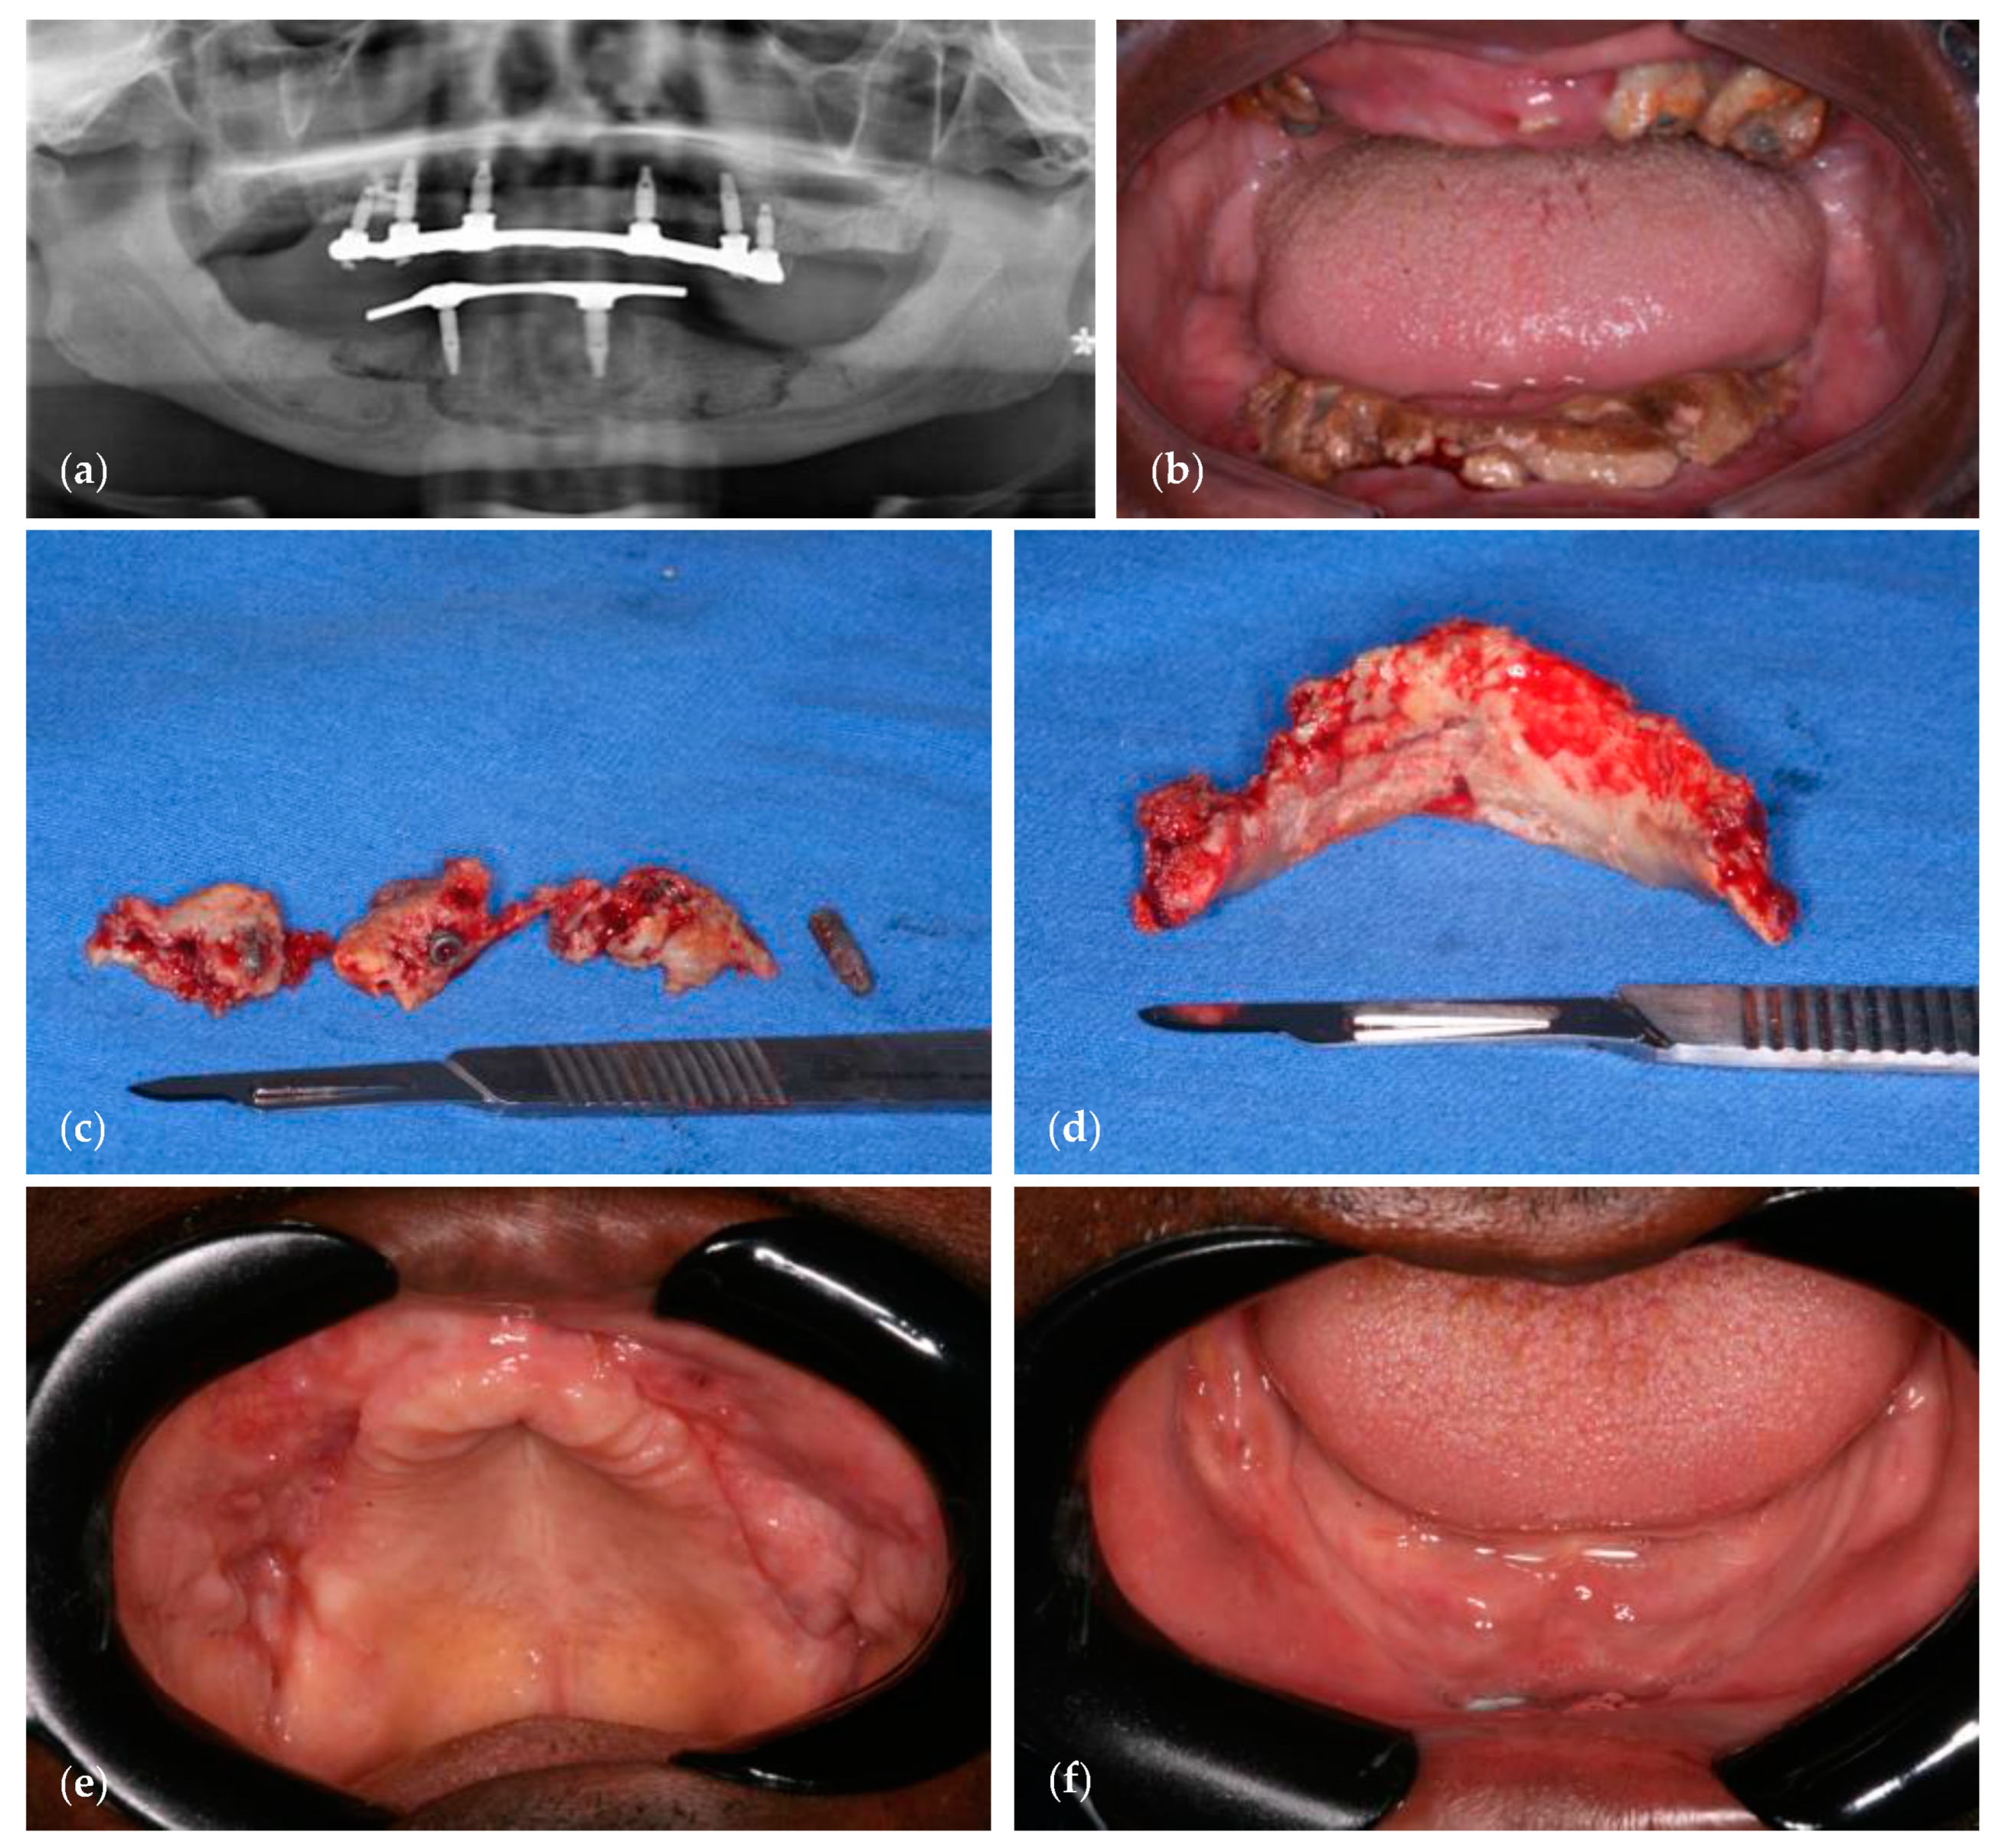

4. MRONJ following Implant Placement—A Case Report